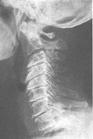

颈椎病又称颈椎综合征,是一种以退行性病理改变为基础的疾患。随着年龄的增长,发病率也逐年增加。有统计表明,50岁左右的人群中大约有25%的人患过或正患此摘,60岁左右则达50%,70岁左右几乎为100%,可见此病是中、老年人的常见病和多发病。

所谓颈椎病,其大致含义是:颈椎间盘退变本身及其继发性的一系列病理改变,如椎节失稳、松动;髓核突出或脱出;骨刺形成;韧带肥厚和继发的椎管狭窄等,刺激或压迫了邻近的神经根、脊髓、椎动脉及颈部交感神经等组织,并引起各种各样症状和体征的综合征。

颈椎位于头部、胸部与上肢之间、又是脊柱椎骨中体积最小,但灵活性最大、活动频率最高、负重较大的节段,由于不承受各种负荷、劳损,甚至外伤,所以极易发生退变。大约30岁之后,颈椎间盘就开始逐渐退化,含水量减少,并伴随年龄增长而更为明显,且诱发或促使颈椎其它部位组织退变。生物力学角度来看,第5—6、第6—7颈椎受力最大,因此,颈椎病的发生部位在这些节段较为多见。